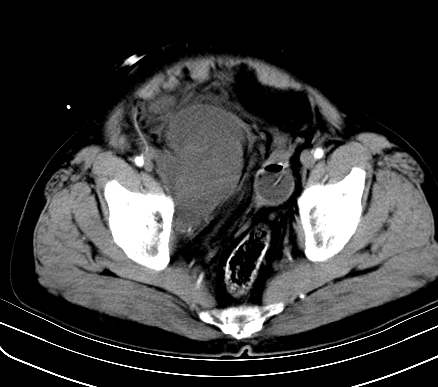

标题: CT19729B:男,74岁,因腿疼就诊,查体触腹部肿物,

增强扫描

动脉期

【ct表现】

1、肿块巨大,往往位于腹膜后,长大后才引起症状而就诊;那么位于腹膜后的肿瘤80%为恶性肿瘤。

2、实性肿瘤,增强扫描轻度不均强化,实性肿瘤一般不是好东西。

3、肿瘤边缘似见少许脂肪样密度。

4、腹膜后未见肿大淋巴结,但肿瘤于临近的肠管及组织接触紧密。

【诊断】

腹部占位,考虑位于腹膜后的恶性肿瘤,脂肪肉瘤(实体型)可能性大。